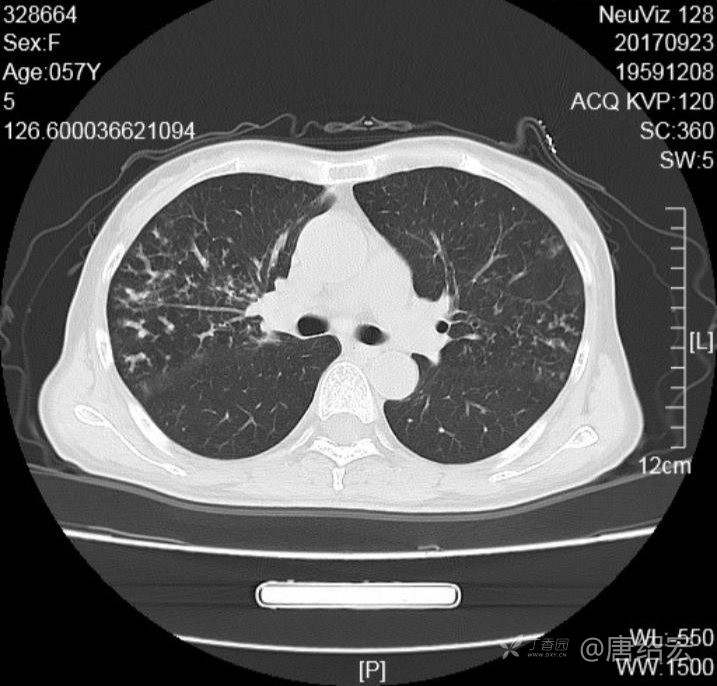

中年女性满肺树芽征还有支气管扩张,考虑什么疾病?

女,57岁,

主诉:发热、咳嗽、咯黄痰,胸闷3天入院。